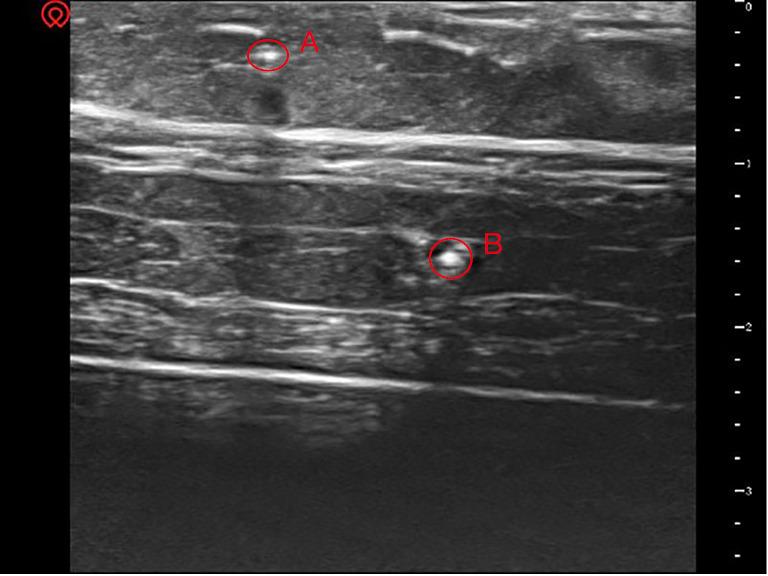

Excellent needle visualization is critical for the safety and success of ultrasound-guided puncture procedures. However, optimal visualization is often challenging when a needle is inserted at a steep angle via in-plane technique. We hypothesized that a water cushion filled under the probe would result in better needle visualization via artificial beam steering during the ultrasound-guided in-plane technique. We simulated human soft tissue with pork and two targets with rigid needles. A water cushion was also made beforehand: a surgical glove was filled with an appropriate amount of water. Ultrasound-guided in-plane puncture procedures for the two targets were performed without and with the water cushion under the ultrasound probe. Clear ultrasound images of the needles were captured for objective visualization analysis. The angles between the ultrasound beam and the puncture needle were measured. The visualization of the needle was significantly better at shallow angles than at steep angles. After using A water cushion, the needle was clearly displayed again at a steep insertion angle. During the ultrasound-guided in-plane technique, needle visualization at a steep insertion angle can be improved by artificial beam steering generated with a water cushion.

出色的针可视化对于超声引导穿刺手术的安全性和成功率至关重要。然而,当通过平面内技术以陡峭角度插入针时,最佳可视化通常具有挑战性。我们假设在探头下方填充水垫将通过超声引导平面内技术期间的人工束转向导致更好的针可视化。我们用猪肉模拟人体软组织并用刚性针模拟两个目标。还预先制作了一个水垫:用手术手套填充适量的水。在超声探头下方有和没有水垫的情况下,对两个目标进行超声引导平面内穿刺手术。捕获针的清晰超声图像以进行客观可视化分析。测量超声束与穿刺针之间的角度。在浅角度下针的可视化明显优于在陡峭角度下。使用水垫后,在陡峭的插入角度下针再次清晰显示。在超声引导平面内技术期间,通过用水垫产生的人工束转向可以改善在陡峭插入角度下的针可视化。